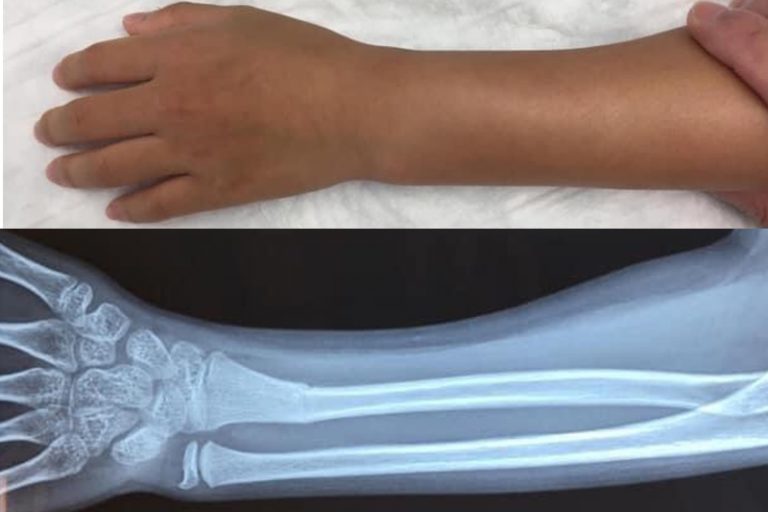

小童的骨質軟而有彈性,不用很大外力就能折彎,因此稍一不慎在耍樂蹦跳期間跌倒或從稍高位置跌下就有可能造成骨折。

常見會有外觀變形、彎曲的情況

醫生會先以X光去確定受傷位置和骨折的嚴重程度